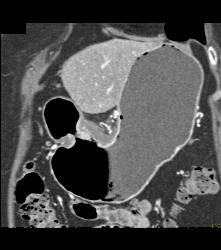

Antral Carcinoma